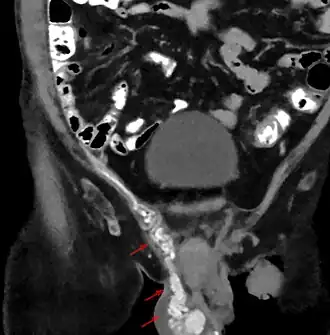

![]() Un varicocele visto mediante tomografía computarizada. Se pueden ver las venas bien desarrolladas a lo largo del cordón espermático. | ||